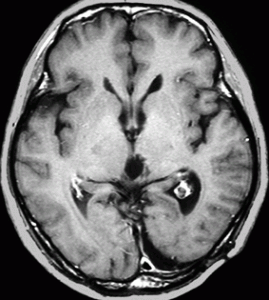

水頭症で発症した6歳児で,4cmくらいある大きな松果体芽腫でした。大学病院で第3脳室開窓術と生検術をして,脳脊髄照射30グレイ(20分割),局所60グレイ(35分割)の放射線治療が行われました。さらにシスプラチンを基剤とした化学療法が3コース行われましたが,放射線で縮小した腫瘍は少し増大してしまいました。

放射線化学療法後の画像です。腫瘍境界は不明瞭(左)で,腫瘍内出血(中央)して,左の視床に浸潤しています。かなりリスクは高いのですが,これを開頭手術で全摘出しました(右),この時点で完全寛解 CR です。この後にさらに化学療法と幹細胞移植(PBSCT,大量化学療法)が加えられました。